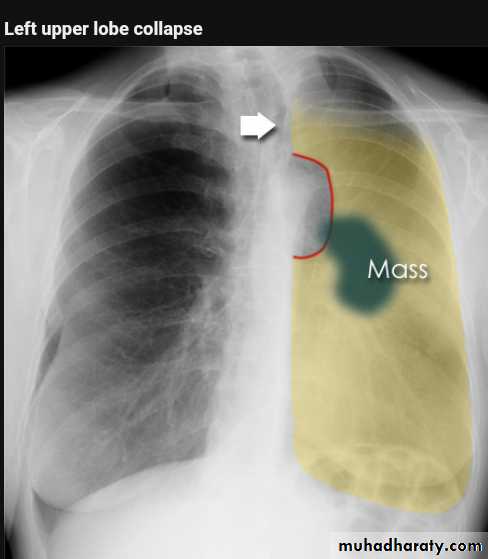

Left upper lobe collapse has distinctive features but can be challenging to identify on chest radiographs by the uninitiated.

Radiographic features

The left upper lobe collapses anteriorly becoming a thin sheet of tissue apposed to the anterior chest wall, and appears as a hazy or veiling opacity extending out from the hilum and fading out inferiorly . It thus reverses the normal slight increase in radiographic density seen as you move down the lung (due to increased thickness of the chest soft tissues).

Parts of the normal cardiomediastinal contour may also be obliterated where the left upper lobe, particularly the lingula abut the left heart border. The anterior parts of the aortic arch are also often obliterated from view.

In some cases the hyperexpanded superior segment of the left lower lobe insinuates itself between the left upper lobe and the superior mediastinum, sharply silhouetting the aortic arch and resulting in a lucency medially. This is known as the luftsichel sign.

The left hilum is also drawn upwards, resulting in an almost horizontal course of the left main bronchus and vertical course of the left lower lobe bronchus.

Non-specific signs indicating left sided atelectasis will also be present, including:

elevation of the hemidiaphragm

'peaked' or 'tented' hemidiaphragm: juxtaphrenic peak sign

crowding of the left sided ribs

shift of the mediastinum to the left

On lateral projections the left lower lobe is hyperexpanded and the oblique fissure displaced anteriorly. There is associated increase in the retrosternal opacity.

Radiology of BGCA

The appearance depends on the location of the lesion.1.The more central lesions may merely appear as a bulky hilum, representing the tumor and local nodal involvement the lesion is irregular in outline have spiky or sun ray spiculation .

2.Lobar collapse may be seen due to obstruction of a bronchus. When the right upper lobe is collapsed and a hilar mass is present, this is known as the Golden S sign.